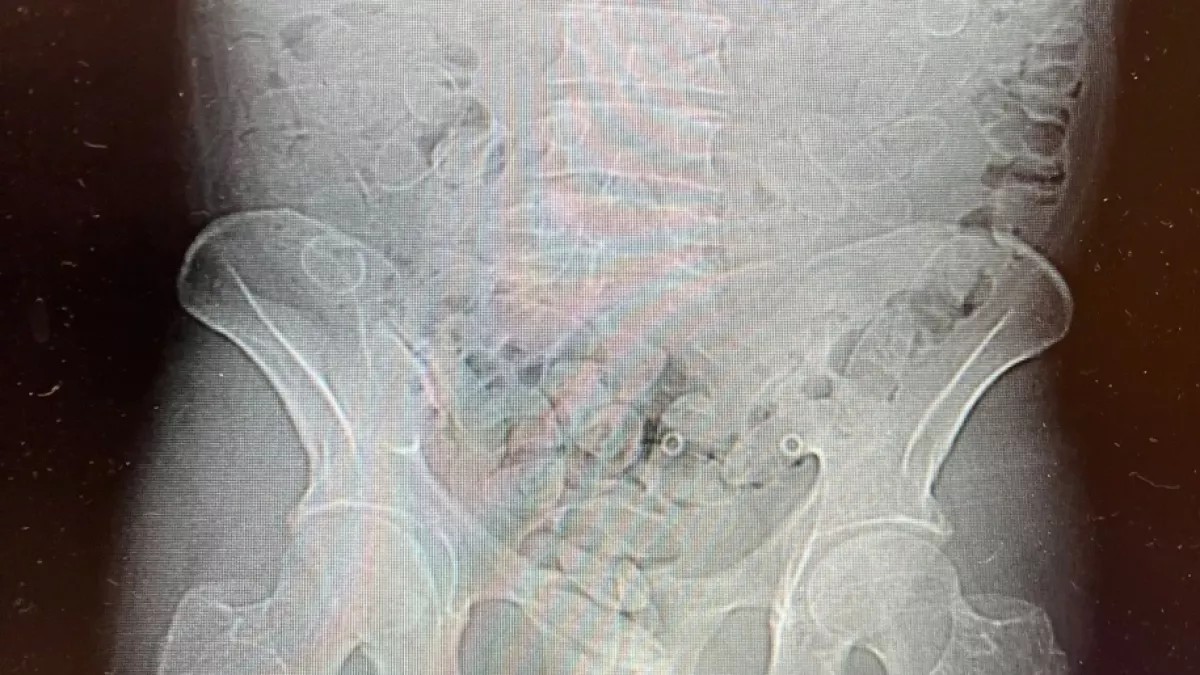

Тексеру нәтижесі таңғаларлық болды: ер адамның ағзасынан кокаин салынған 88 капсула табылды. Контрабанданың жалпы құны шамамен 300 мың злотыйға (Польша ұлттық валютасы) бағаланып отыр.